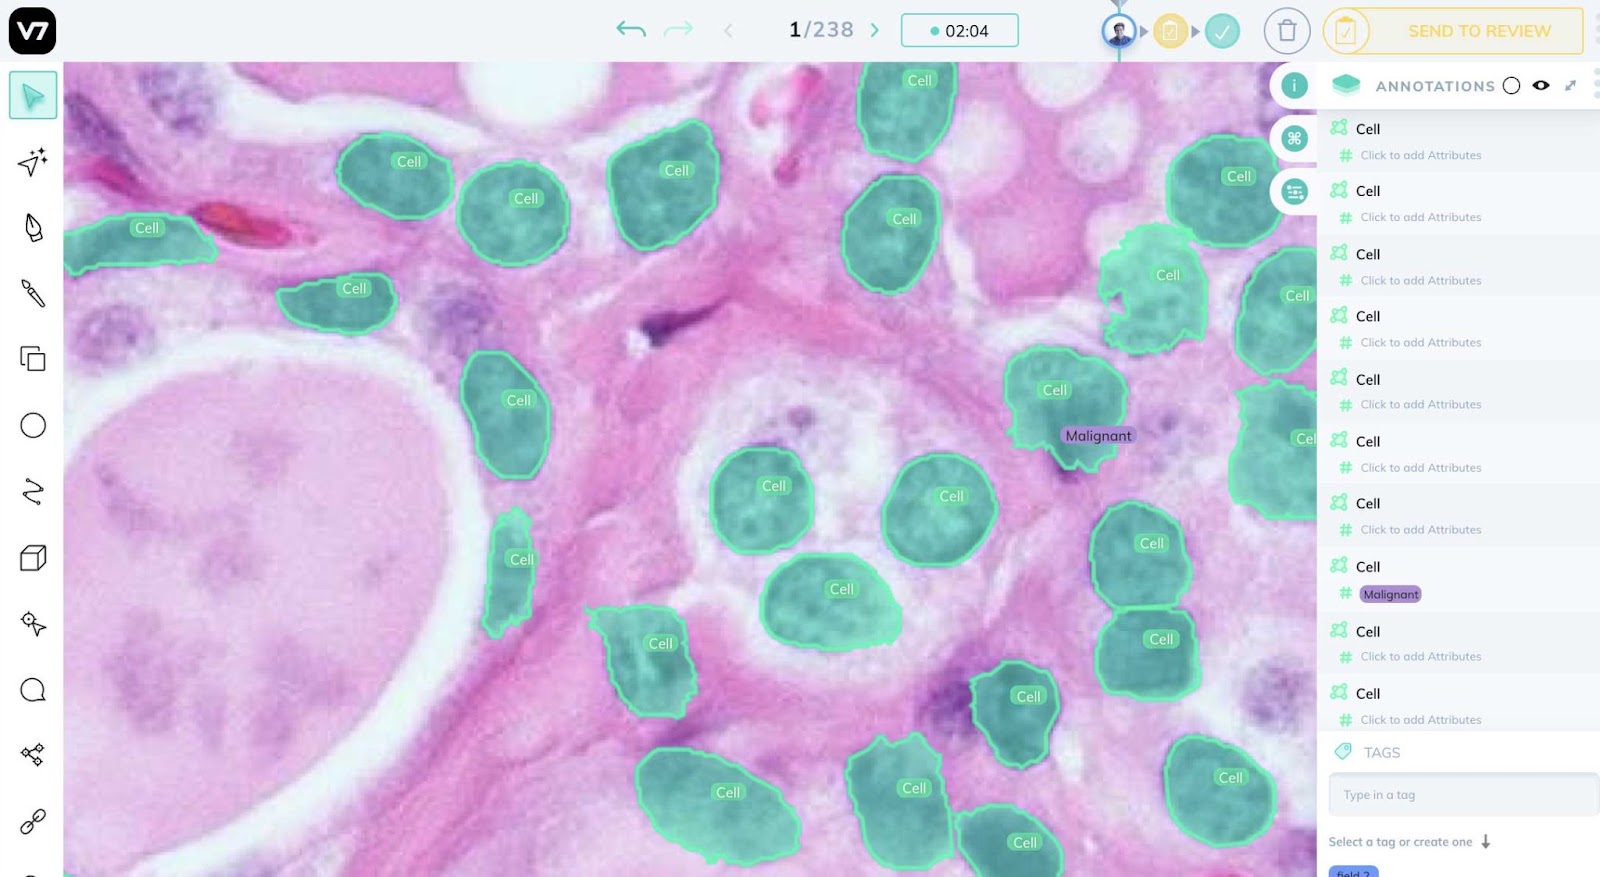

癌症检测

图像识别允许医生通过比较图像中的癌细胞和非癌细胞来识别异常和变化。

自动检测允许使用来自磁共振成像 (MRI) 扫描的数据更快地诊断癌症。计算机视觉已经成功应用于乳腺癌和皮肤癌的检测。

数字病理学

由于全幻灯片成像 (WSI) 数字扫描仪的普及,计算机视觉现在可以处理医学图像数据以检测和识别所显示的病理类型。

它用于:

- 图像分析和解释

- 样本组织的详细检查

- 与早期病例匹配的病理类型

- 诊断准确性和早期发现

计算机视觉增强的数字病理学提高了诊断的准确性和效率,帮助医生节省宝贵的时间并做出更明智的决策。